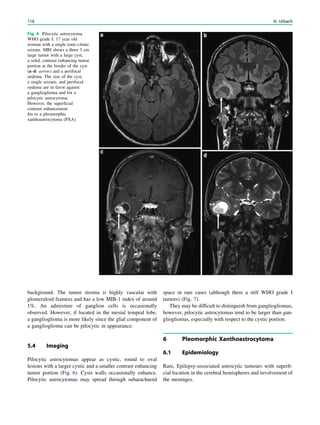

Fig. 1 Digital photogram of the brain surface before placement of a

subdural 8 9 8 grid. A second photogram was taken after grid

placement and digitally replaced by a schematic drawing detailing the

results of electrical stimulations and ictal/ intraictal EEG activity. Blue

grid contacts represent the eloquent zone, which is the motor cortex in

this case. The black area represents the epileptogenic lesion, defined

as the radiographic lesion that causes the seizures. The yellow area is

the seizure onset zone, defined as the area from which the clinical

seizures are generated. The seizure onset zone is often, but not

necessarily, congruent with the epileptogenic zone, defined as the

cortex area indispensable for the generation of seizures

H. Urbach (ed.), MRI in Epilepsy, Medical Radiology. Diagnostic Imaging,

DOI: 10.1007/174_2012_557, Ó Springer-Verlag Berlin Heidelberg 2013

21

To achieve freedom from seizures following epilepsy

surgery, in some but not all cases not only the epileptogenic

lesion itself but also some perilesional tissue must be

removed. Conceptually, it is the epileptogenic area that has

to be removed, which is defined as cortical area indis-

pensable for the generation of seizures. Practically, it is the

Fig. 2 Epileptogenic lesion and symptomatogenic zone. A 40-year-

old woman suffered from complex focal seizures with a fearful face

and body rocking. The symptoms thus pointed to the mesial frontal

lobe as the origin. MRI shows right-sided hippocampal sclerosis

(a, arrow). Simultaneous video and EEG recordings from interhemi-

spheric (c) and convexity strip and intrahippocampal depth (b) elec-

trodes show seizures starting in the right hippocampus (d, arrow).

Clinical symptoms start around 1 s afterwards (d, asterisk)

22 H. Urbach

seizure onset zone which it is intended to be removed, and

this is defined as the brain area in which ictal EEG activity

starts. The epileptogenic lesion usually shows at least some

overlap with the seizure onset zone and is therefore a good

indicator for its localization (Fig. 1).

Other frequently used terms are irritative area, defined as

the brain area with interictal EEG activity, eloquent cortex,

defined as the cortex area with important functions such as

language, motor, and visual field functions, and symptoma-

togenic area, defined as the brain area in which epilep-

togenic activity leads to clinical symptoms. If epileptogenic

activity spreads rapidly, the epileptogenic lesion and the

symptomatogenic area can be far from each other (Fig. 2).